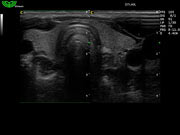

D3C60L 3.5МГц, конвексный.

2.0МГц - 5.8 МГц. Применения: абдомиальное обследование, акушерство, гинекология, обследование районной блокады нерва, осуществление и управление биопсией. |